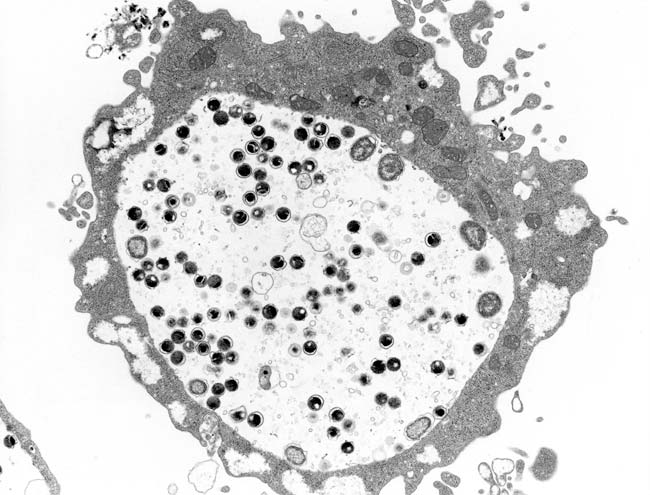

Chlamydia trachomatisの電子顕微鏡像

(参考)国立感染症研究所

https://www.niid.go.jp/niid/ja/kansennohanashi/423-chlamydia-std-intro.html